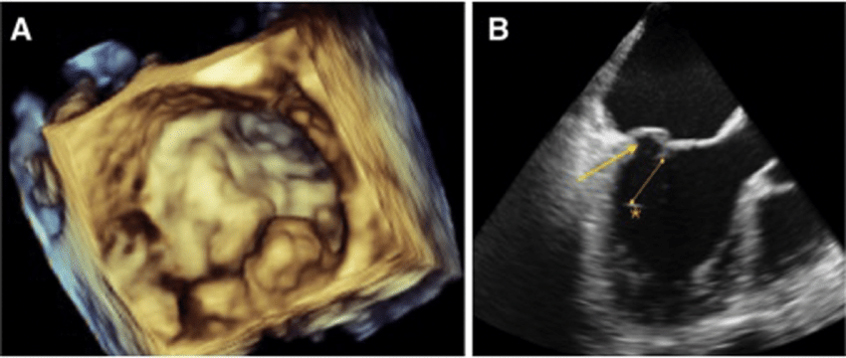

1. Evaluating heart function: It helps assess how well the heart is pumping blood and how efficiently the heart valves are functioning.

2. Diagnosing heart conditions: Echocardiograms can detect abnormalities such as heart valve problems, congenital heart defects, and enlargement of the heart chambers.